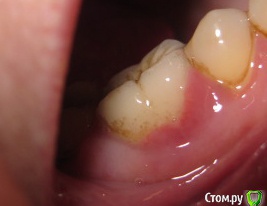

Sparrow Опубликовано 27 февраля, 2018 Поделиться Опубликовано 27 февраля, 2018 (изменено) Уважаемые специалисты.Прошу Вашего мнения относительно моей ситуации. 5 месяцев воспалена десна и сосочек между зубами.При надавливании на край десны из под десны появляются выделения белого цвета в небольшом количестве (буквально по 1 мм вдоль кромки десны). Боли нет ни в десне ни в зубе.Зуб не шатается. На зубе коронка со штифтами - ставили 14 лет назад.При обнаружении воспаления обратилась к стоматологу.Сделан снимок - на снимке ничего не обнаружено - вывод местное воспаление. К такому же выводу пришли впоследствии еще три специалиста - снимок делали еще 2 раза - ничего не находили . За это время (5 месяцев) было сделано 2 чистки - 1 локально - ультразвук под десной - сильно кровоточило и сосочек на следующий день "сдулся" до нормального размера,но выделения остались и через время десна снова увеличилась.Вторая чистка - полностью полость рта. Состояние десны осталось прежним.Выделения есть.Применила уже все возможные варианты полосканий - хлоргексидин-мирамистин-ромашка-сода-парадонтакс-стоматофит - полностью успокоить десну не удается. Обратилась снова к стоматологу. Сделали КТ. Киста на корне зуба и кариес корня под десной. Зуб удалять однозначно или есть еще минимальная возможность его спасти? (мне крайне неудобно показывать вам этот цветной налет на зубах - но это то,что вышло от применения супермягкой щетки Парадонтакс и ополаскивателя Парадонтакс-Экстра за полтора месяца после последней гигиенической чистки) Изменено 27 февраля, 2018 пользователем Sparrow Ссылка на комментарий